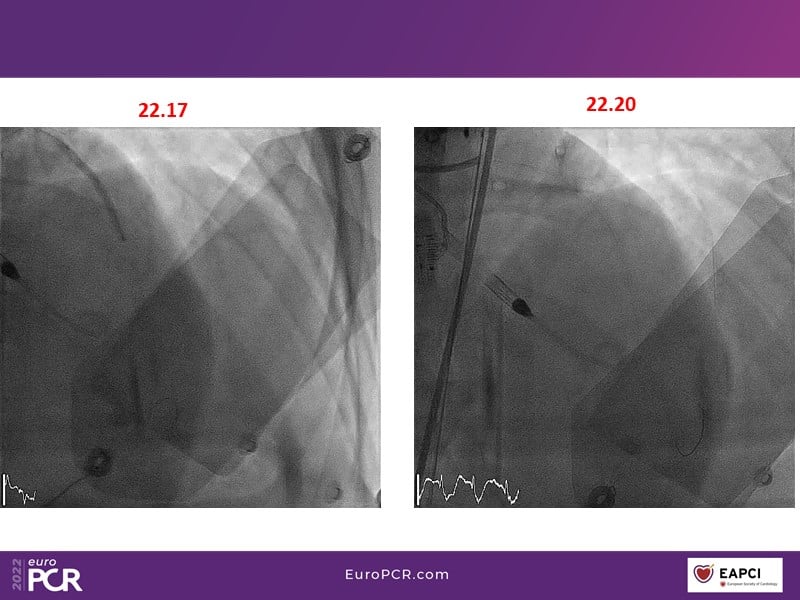

Tailored support for complex PCI and AMI with percutaneous mechanical circulatory support

Watch this EuroPCR 2022 session, in which Javier Escaned, Florim Cuculi, and Norman Mangner present different cases, to learn how standard operating procedures including mechanical circulatory support improve outcomes in patients with complex coronary lesions, discuss new strategies to overcome ischemic reperfusion lesions using percutaneous mechanical circulatory support, and understand the benefits of mechanical circulatory support in AMI patients.